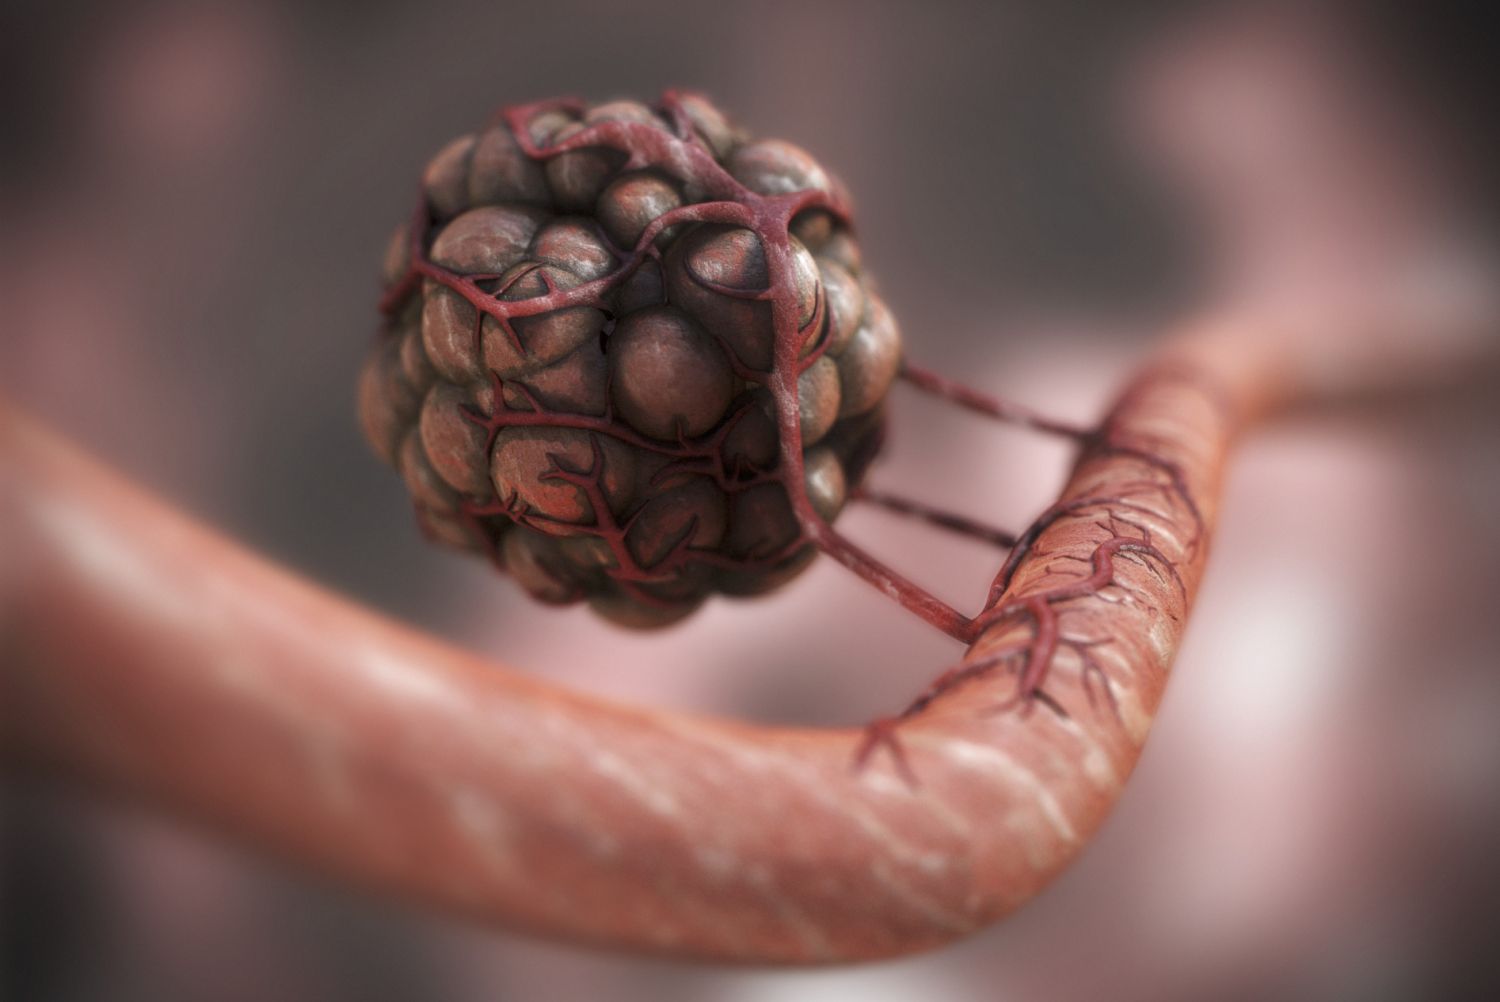

Раковая шишка – это заболевание, которое поражает кожу и слизистые оболочки. Она может возникнуть в различных частях тела и иметь различные внешние проявления. В данной статье мы представляем вам многочисленные фотографии раковых шишек, чтобы вы могли узнать, как они выглядят.

Раковые шишки могут возникать не только на лице, но и на других частях тела. На фотографиях вы можете увидеть примеры раковых шишек на шее, руках, ногах и туловище. Обратите внимание на различные формы и размеры раковых шишек, а также на их внешний вид.